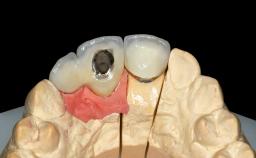

Replacement of Two Central Incisors and One Lateral Incisor with a Fixed Dental Prosthesis on Two Bone-Level Implants

A 38-year-old woman presented with an esthetically unacceptable fixed partial denture replacing teeth 11, 21, 22. She had lost these teeth due to trauma when she was a child. The patient was not in pain but very concerned based on her previous experience that dental treatments had never satisfied her esthetic expectations. She was in good general health and reported no regular medications. No periodontal disease was noted despite the fact that the buccal flange of the prosthesis impeded cleaning of the tooth abutments. The patient did not smoke and complied with home maintenance requirements, as evidenced by her good oral hygiene status.